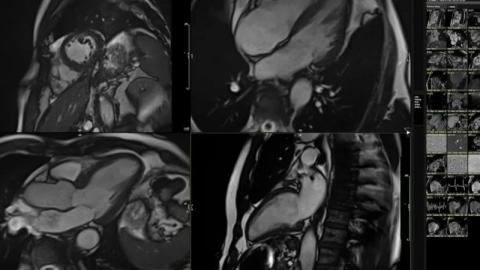

وی، اظهار کرد: تصویربرداری پرتو مغناطیسی یا همان اسکن ام‌آرآی قلب بعد از کمی تحرک بدنی هم بخشی از روند ارزیابی بود. نشانه‌های اولیه پیر شدن زودرس قلب گاهی آن قدر ظریف و نامحسوس است که حتی ممکن است از دید متخصصان قلب هم پنهان بماند. اما هوش مصنوعی قادر است این کار را انجام دهد چون تصاویر اسکن‌های ۴۰ هزار نفر در شرایط مختلف از نظر سلامت قلبی را همراه با وضعیت سلامت خودشان برای رجوع و مقایسه در اختیار دارد. سیستم صدها مورد جزیی و کوچک را در تکان‌های سه‌بعدی اسکن ام‌آرآی من بررسی می‌کند و با تصاویر پنج‌هزار نفر دیگر در سنین مختلف مقایسه می‌کند که زندگی سالمی داشته‌اند.